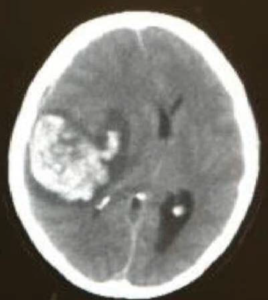

相关案例案例(一):孕期中的女性两个分别15、16岁的少女,一向健康、没有头痛症状,两个案例分别在怀孕初期及中期,突然患上严重大脑出血性中风,剧烈头痛后急速昏迷休克,在紧急脑外科开颅手术清除瘀血及减低颅内压后,两名少女和他们的小孩完全康复,没有任何后遗症。 另一案例是一位39岁的怀孕后期的女士,就发生在婴儿要出世而作动的一晚,她的丈夫英勇果断的把她和婴儿从鬼门关中拯救出来,婴儿现在已是一个健康和可爱的孩子了。无奈39岁的女士,由于动静脉畸形血管瘤破裂引至严重的大脑功能损伤却变成了植物人,医生尝试用过每一种治疗方案亦不果,在医院卧床了五年才去世。 | ![]() |

![]() | |